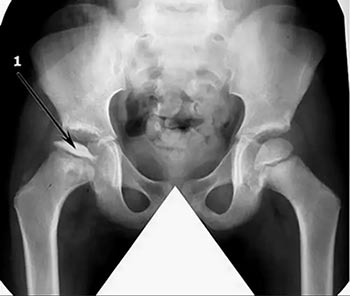

Вначале болезни диагноз поставить тяжело, поскольку симптоматика размыта. Начиная со второй стадии признаки недуга четко видны на рентгенологическом снимке.

Однако рентгенологические признаки в виде расширения щели сустава, очагов деструкции субхондральной пластинки головки бедренной кости появляются слишком поздно, когда у пациентов практически исчезает болевой синдром, а хромота нарастает. На этой стадии пациенты нуждаются в проведении оперативного лечения [6].

Диагностика болезни Пертеса прежде всего проводится с помощью рентгена. При этом точно определяются стадии деформации недуга.

Фото выполняется сразу в нескольких проекциях, чтобы ортопед мог подробно все рассмотреть. Для подтверждения диагноза назначается УЗИ, томография и артроскопия.